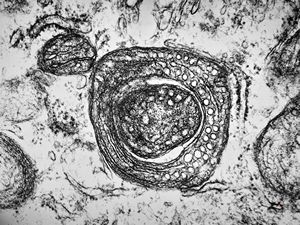

M,7m. | a formation of Birbeck granule(Langerhans granule, X-granule) - skin, histiocytosis X

M,7m. | Birbeck granules (Langerhans granules, X-granules) - skin, histiocytosis X

M,1y. | Birbeck granules (X-granules) - skin, histiocytosis X

M,1y. | Birbeck granule (X-granule) - skin, histiocytosis X